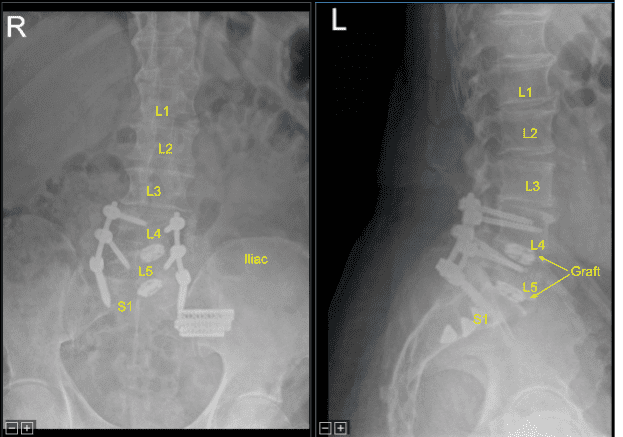

Additional CT scans were performed showing correct positioning of all the pedicle screw hardware. Neuromonitoring signals were stable. Next, we decorticated bilateral transverse processes and facet joints including sacral ala from L4 to S1 bilaterally with electric high-speed drill for the arthrodesis. The wound was irrigated copiously.

Precut-precontoured titanium rods were selected, contoured further and placed across the tulips from L4 to S1 bilaterally and secured with locking caps which were all final tightened with a torque and anti torque device. AP and lateral fluoroscopy was used to confirm appropriate sizing and positioning of the rods.

Next, morselized autograft resected from spinous processes of L4 and L5, which was morselized in the bone mill, was mixed with demineralized bone matrix allograft putty as well as bone morphogenic protein. We aspirated iliac crest bone marrow through a separate incision created for the Schanz pin with a bone marrow aspirator. This was mixed as well.

These were packed in lateral gutters and across the facet joints after decortication from L4 to S1 for arthrodesis.The wound was irrigated clear. Hemostasis was obtained with bipolar electrocautery and bone wax.